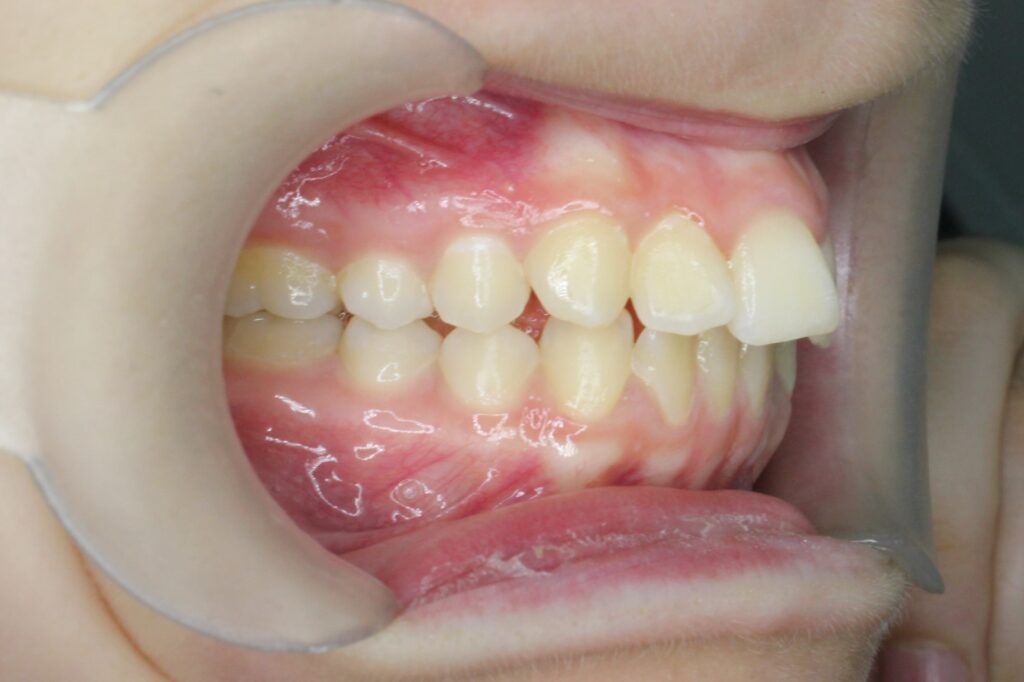

Ситуация до лечения

Жалобы: Пациентка обратилась с жалобами на неровное положение передних зубов.

Диагноз: дистальный прикус, сужение верхнего и нижнего зубных рядов, скученность фронтальной группы зубов на верхней и нижней челюсти.

пациент до лечения брекетами